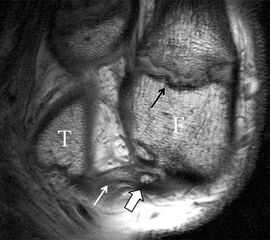

Da also die hintere Syndesmose an der posterioren Tibia inseriert, entspricht eine Fraktur oder Infraktion des hinteren Volkmann`schen Dreiecks funktionell einem knöchernen Ausriss des Ligamentum tibiofibulare posterius (Abb. 18 a und b). Aufgrund der Koinzidenz von Syndesmosenläsionen mit Innenbandverletzungen ist bei der Beurteilung gesondert auf solche zu achten.

b. T2 fs axial. Infraktion des hinteren Volkmann‘schen Dreiecks (schmale, weiße Pfeile). Hier inserierende, intakte, hintere Syndesmose (breite, weiße Pfeile).